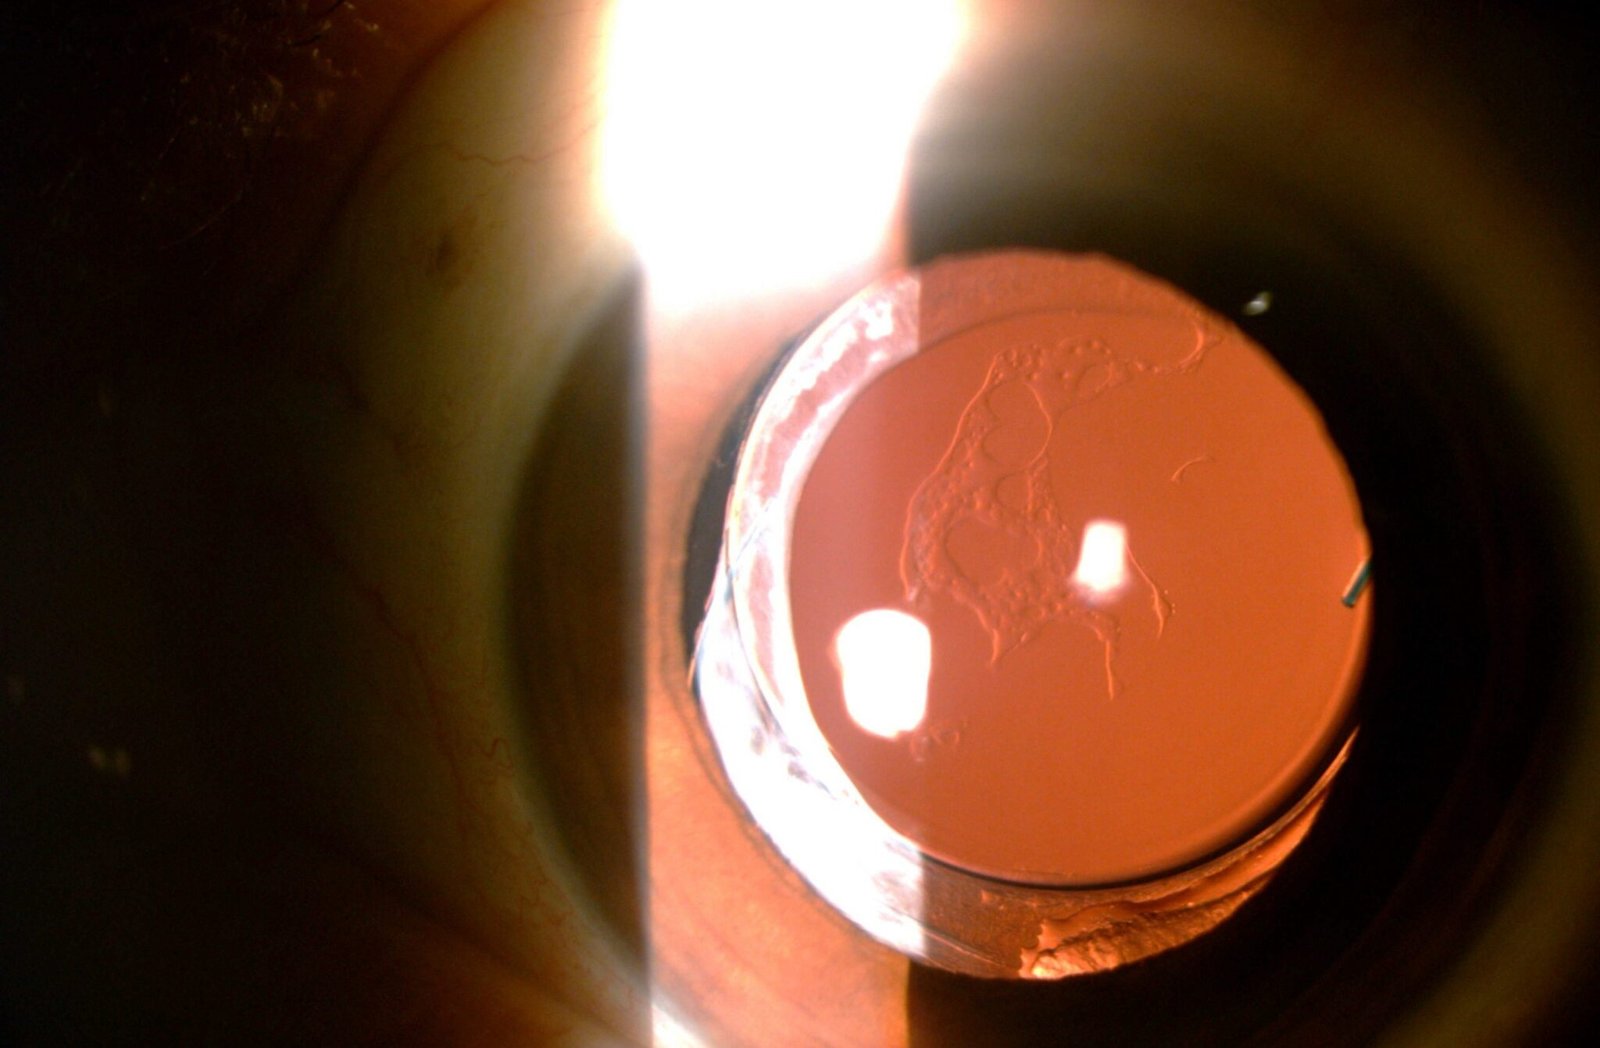

Grading In Ophthalmology Eye Health Nepal

Grading In Ophthalmology Eye Health Nepal What Does Opacification Meaning The process of becoming cloudy or opaque. When a ct scan is taken of the. the meaning of opacification is an act or the process of becoming or rendering opaque. the maxillary sinus is the cavity behind your cheeks, very close to your nose 1. posterior capsular opacification (secondary cataract) is a clouding of the thin membrane. What Does Opacification Meaning.